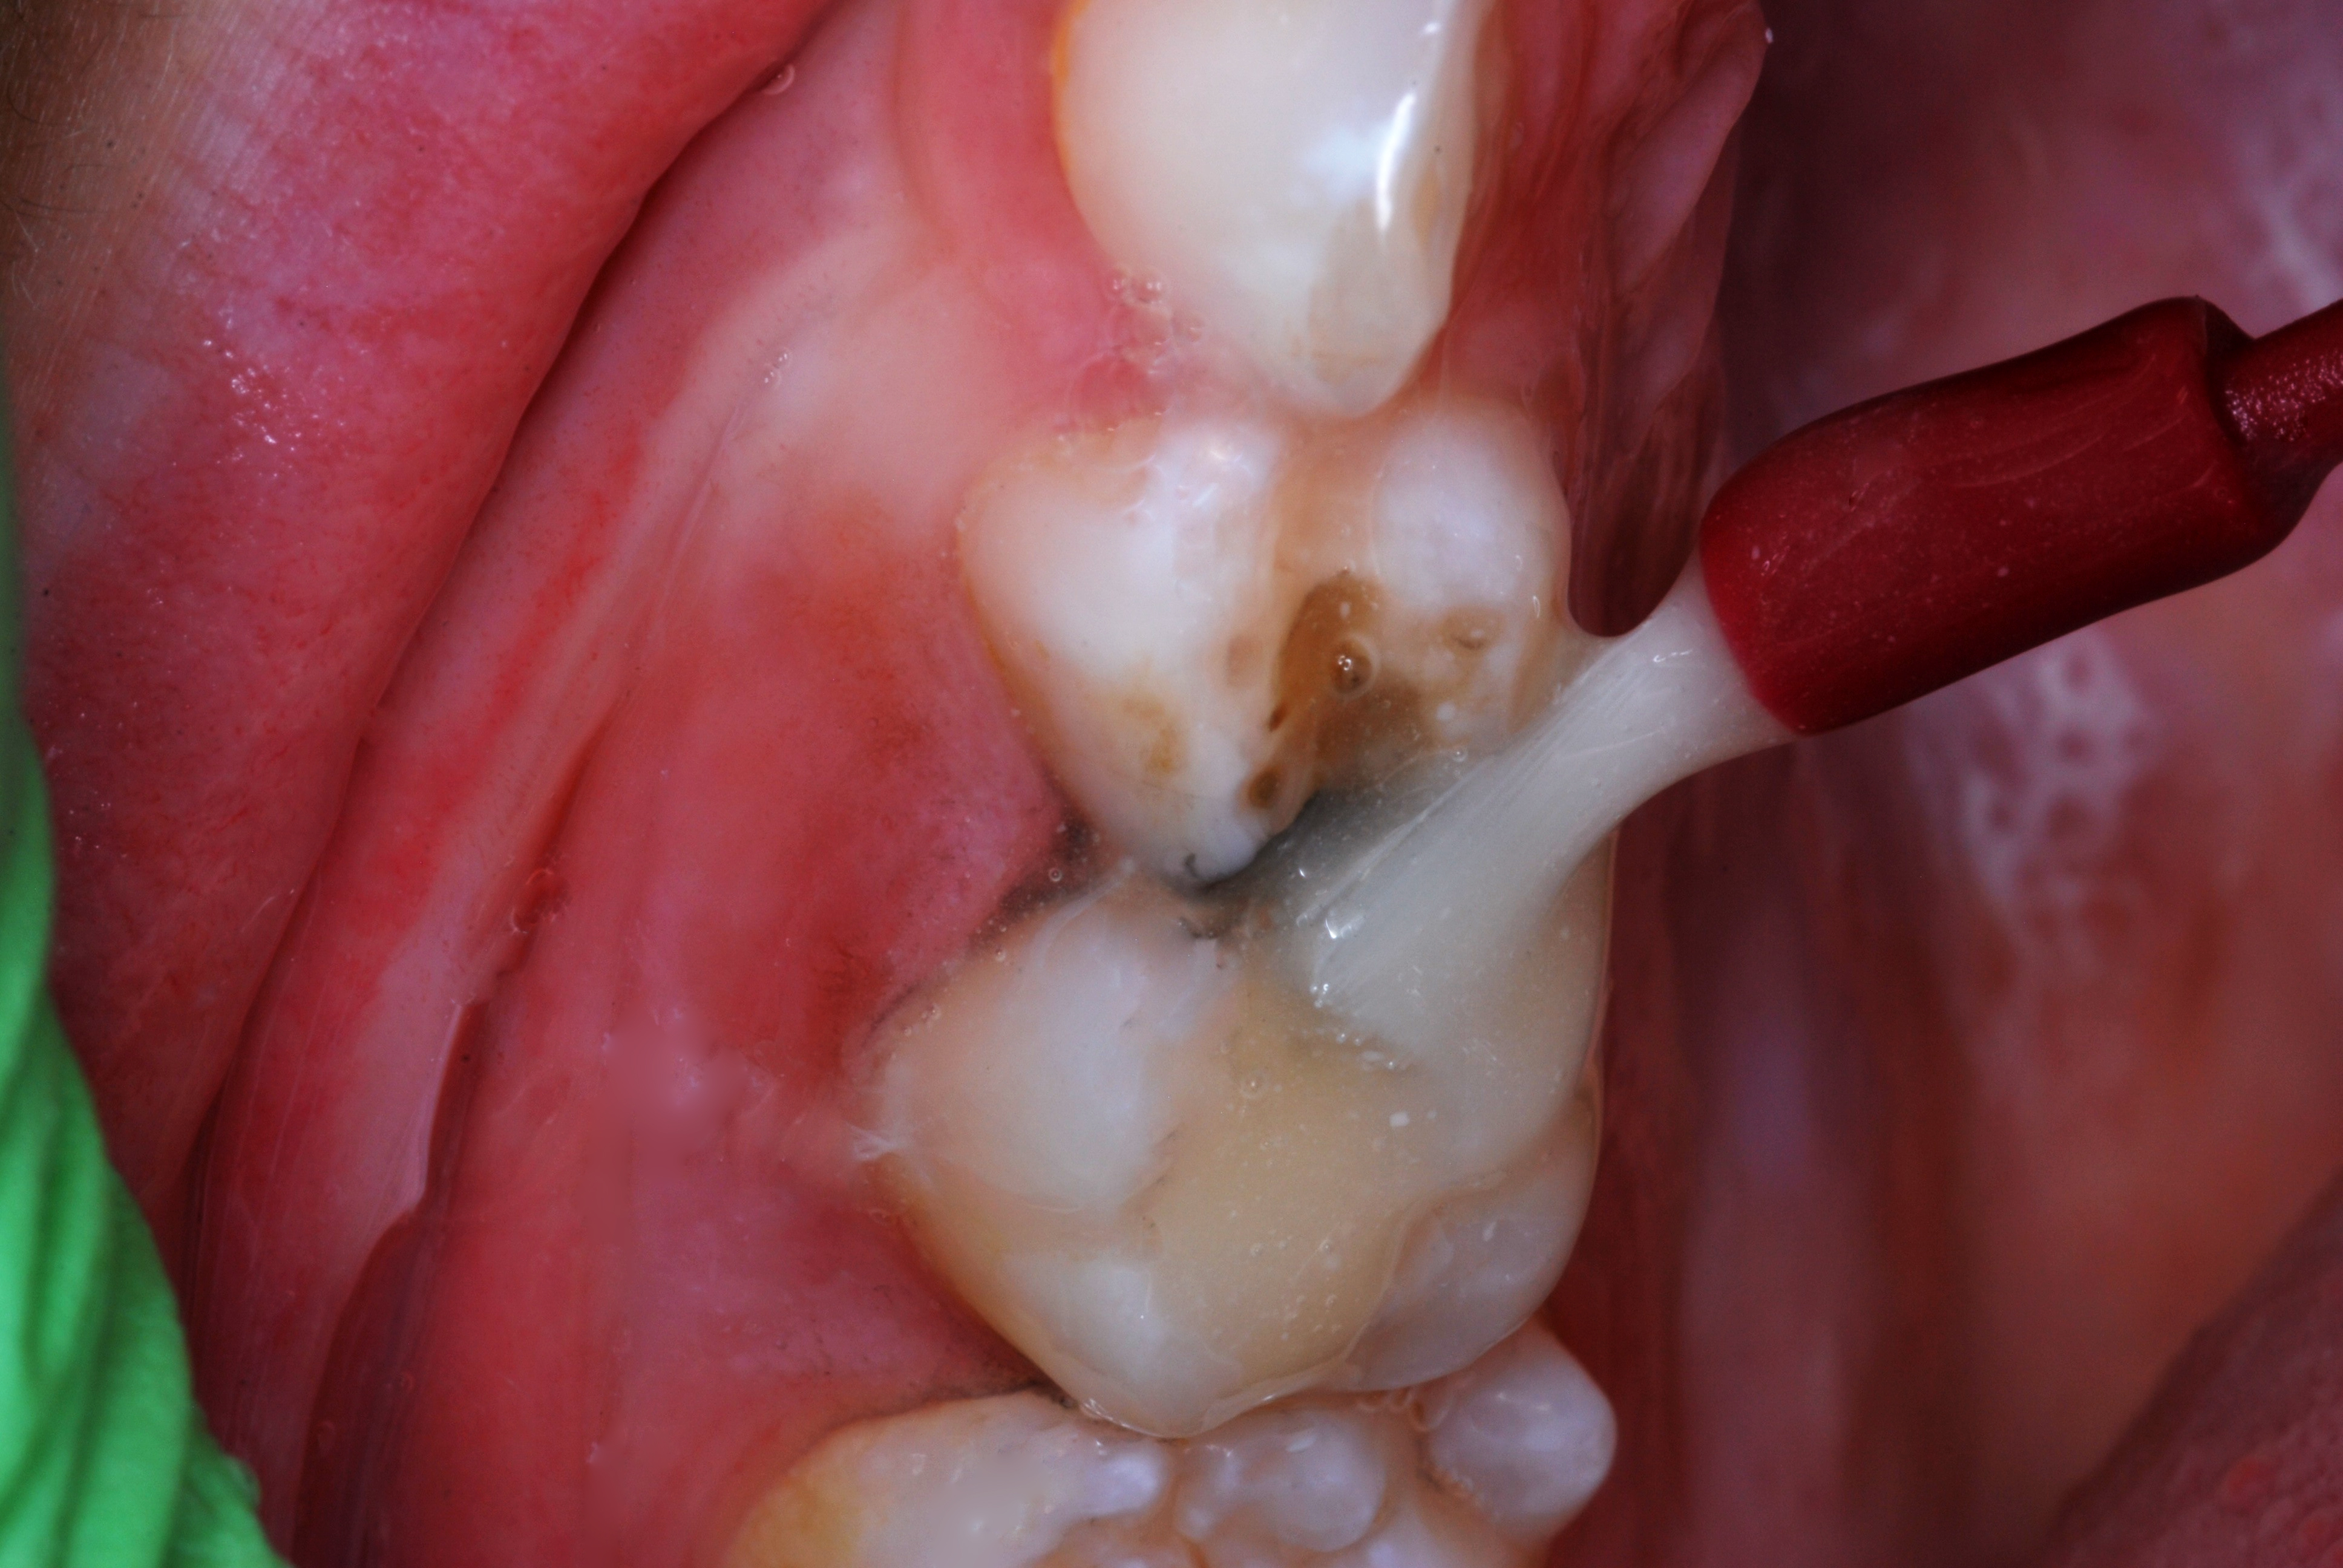

(6.) After exposure of disto-occlusal caries, SDF is applied, followed by a coating of fluoride varnish.

Figure 6